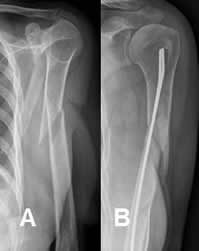

Fig 92. Clavo de Enders.

A: Rx AP. Fractura espiroidea y con angulación en valgo, de la diáfisis humeral.

B: Rx AP. Reducción abierta y fijación intramedular, con clavo de enders.